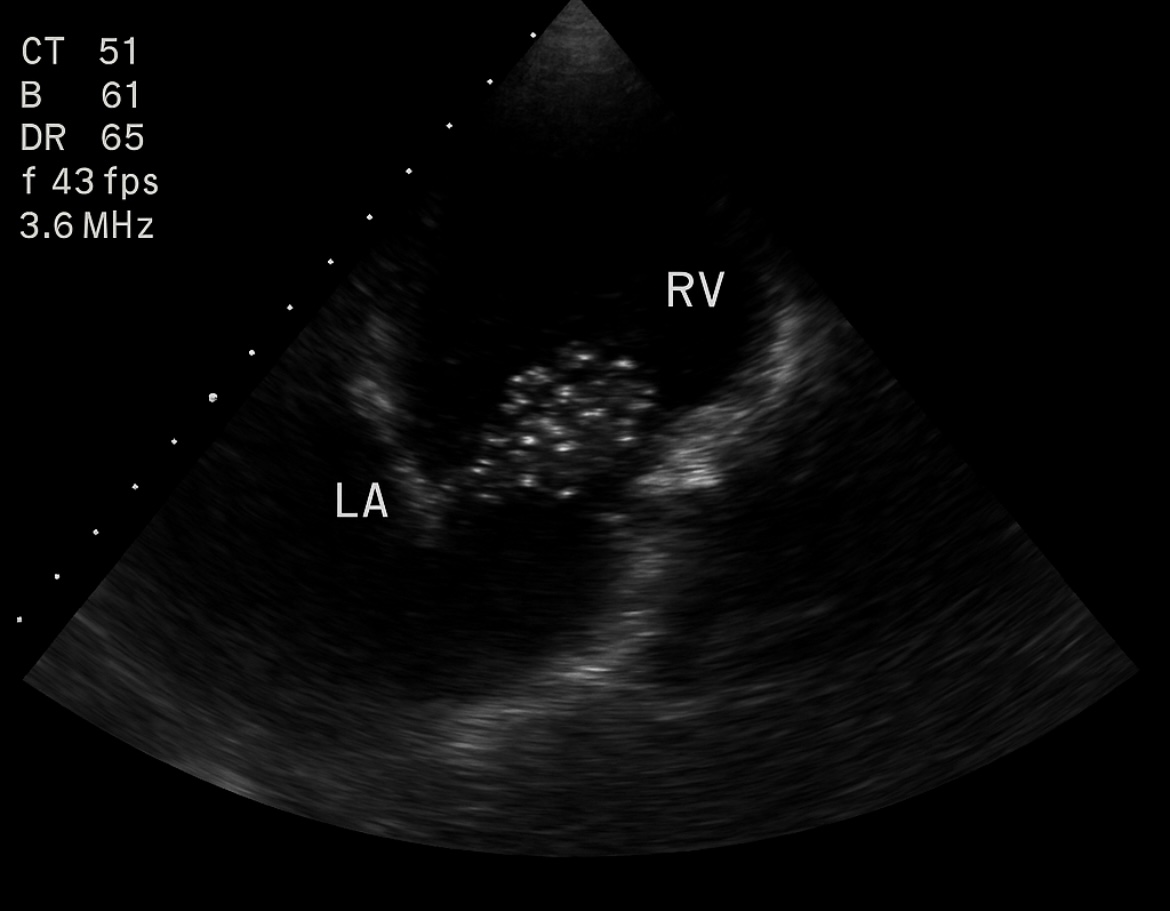

Hallazgos: VD discretamente dilatado. AD y tracto de entrada VD con múltiples microburbujas hiperecogénicas, moviéndose en flujo turbulento. No derrame pericárdico. Vena cava inferior colapsable.